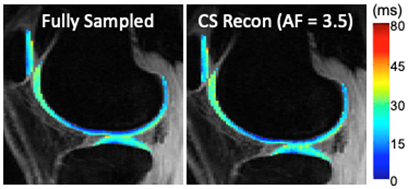

Accelerated Quantitative Knee MRI using Compressed Sensing and Deep Learning

Investigative Team: Jeehun Kim, MS; Mingrui Yang, PhD; Xiaojuan Li, PhD; Naveen Subhas, MD; Carl Winalski, MD; Joshua Polster, MD

External collaborators: University at Buffalo, The State University of New York: Leslie Ying, PhD, Chaoyi Zhang, Hongyu Li

We have developed algorithms combining an advanced CS based reconstruction technique, LAISD, and an advanced parallel imaging technique, JSENSE, and achieved superior quantitative accuracy for T1ρ quantification with AF up to 4. We will further develop model-based CS techniques to take full advantage of the known quantitative model for T1ρ and T2 decay such that the estimated T1ρ and T2 maps are more robust to noise. We are also working on develop novel MR reconstruction algorithm using deep learning techniques. Compared to CS, one advantage of machine learning methods is the fast image reconstruction. With a 15-layer convolutional neural network (CNN), we have reduced the acquisition time 6 times without significantly affecting the image quality, as well as clinical grading and diagnostic capability. We are currently working on developing DL reconstruction algorithm for cartilage relaxation time quantification, for both mono- and bi-exponential decay components.